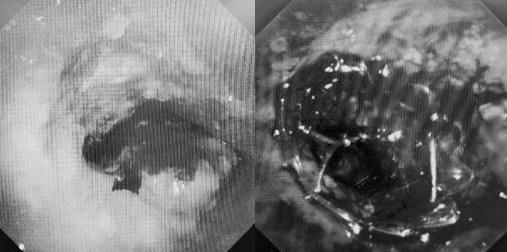

時(shí)間就是生命!了解患者病情后,歐陽(yáng)海峰立刻啟動(dòng)氣道梗阻緊急救治通道,協(xié)調(diào)院前轉(zhuǎn)運(yùn),急診快速入院流程。凌晨患者入院胸部CT顯示,現(xiàn)存唯一的呼吸通道在右主支氣管處,狹窄處僅約3毫米,患者命懸一線!

運(yùn)用呼吸介入技術(shù),軟硬鏡結(jié)合快速開通氣道,是患者目前唯一可行的治療方案,手術(shù)刻不容緩!但存在麻醉后氣道完全塌陷閉合、大出血、窒息等巨大風(fēng)險(xiǎn)。患者此前接連轉(zhuǎn)診3家醫(yī)院,均建議保守支持治療或轉(zhuǎn)院。歐陽(yáng)海峰詳細(xì)了解患者病史,全面評(píng)估影像檢查結(jié)果后,決定盡快進(jìn)行手術(shù),組織醫(yī)護(hù)團(tuán)隊(duì)對(duì)患者進(jìn)行持續(xù)密切監(jiān)測(cè),充分保障其術(shù)前安全。

患者入院第二天,在麻醉手術(shù)中心全力配合下,歐陽(yáng)海峰帶領(lǐng)呼吸介入團(tuán)隊(duì),歷時(shí)40分鐘快速置入硬質(zhì)支氣管鏡、鏟切腫瘤,并順利植入全覆膜TTS支氣管金屬支架。患者氣短癥狀即刻緩解,為患者贏得了寶貴的后續(xù)治療機(jī)會(huì)。